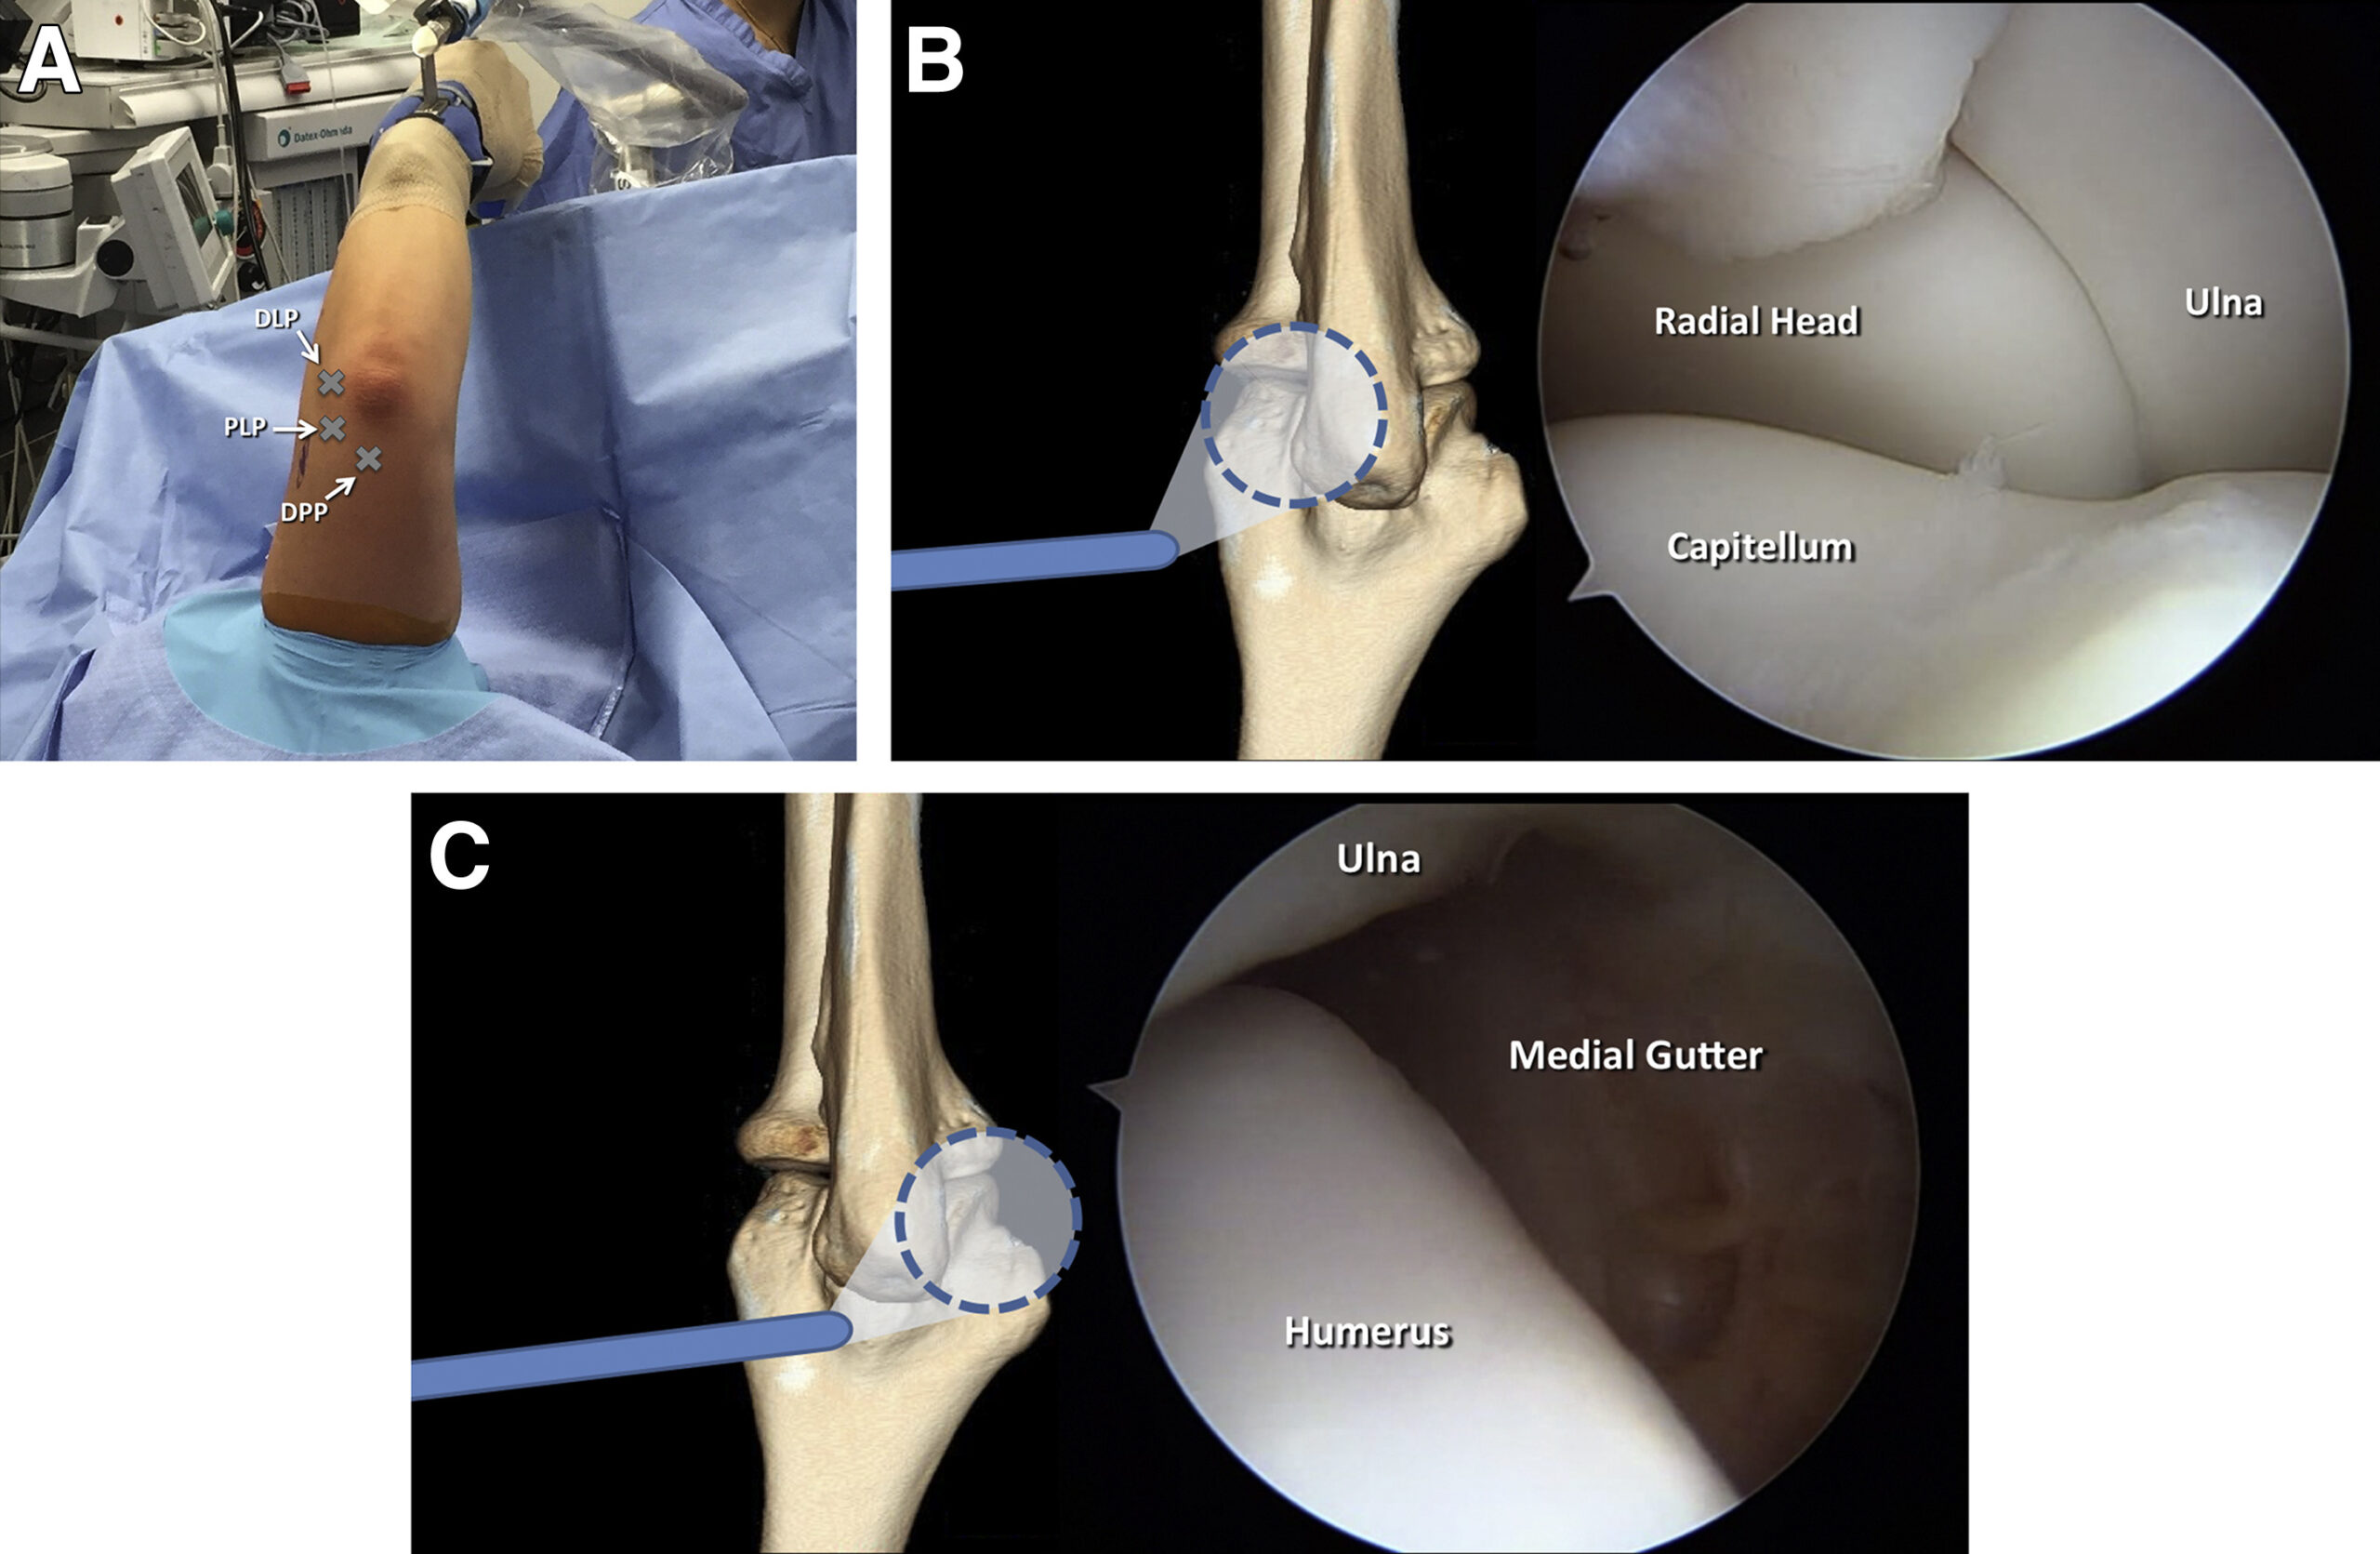

Elbow Arthroscopy

What Is Arthroscopy?

Arthroscopy is a minimally invasive surgical procedure used to diagnose and treat joint problems. During the procedure, a small camera called an arthroscope is inserted into the joint through tiny incisions. This allows the surgeon to view the internal structures on a screen and perform precise repairs using specialized instruments.